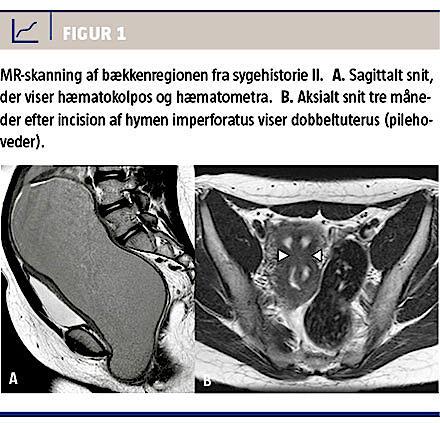

II. En 14-årig pige blev henvist med forstoppelse og en abdominal udfyldning op til umbilicus. Hun havde menstrueret regelmæssigt i to år. En klinisk undersøgelse viste en stor palpabel og indolent tumor i nedre abdomen, mest udtalt mod højre side. Ved inspektion fremtrådte vulva med en blålig frembuling, der var forenelig med hymen imperforatus. En UL-skanning viste en cystisk proces på ca. 20 × 10 cm,

og en højresidig ovariecyste kunne ikke udelukkes. Som bifund fandt man en højresidig renal agenesi.

En supplerende MR-skanning viste desuden uterus didelphys med to separate vaginalrør, højresidig hæmatokolpos og ipsilateral renal agenesi. Denne triade er kendt som Herlyn-Werner-Wunderlichs sygdom (Figur 1). Hymen imperforatus blev incideret, og

der udtømtes ca. 400 ml gammelt blod.